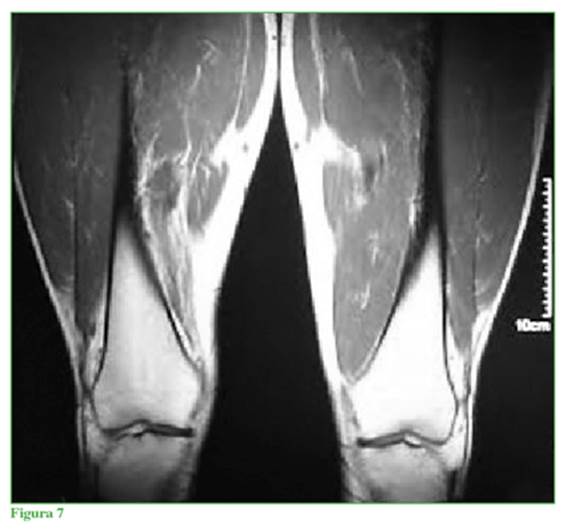

El estudio gold standard es la resonancia magnética nuclear, la que informó ausencia completa del vasto medial oblicuo (VMO) y diagnóstico presuntivo de agenesia completa de ese músculo en cortes axiales, sagitales y coronales en T1 y T2 (Figuras 4 a 8). Cortes coronales a diferentes alturas comparativas de ambos muslos en la región del tercio medio distal (Figuras 5 a 8).

Falta la representación habitual del músculo vasto medial derecho en toda su extensión, sugestivo de hipotrofia grave/agenesia muscular; vasto intermedio derecho, vasto lateral y recto anterior de grosor y señal de resonancia preservada. No se identifican alteraciones del trofismo muscular, ni señal de resolución de los músculos del grupo medial y posterior derecho, ni a nivel del muslo izquierdo. No se observan lesiones ni alteraciones del paquete vascular femoral. Llama la atención una asimetría en la masa muscular de la cara interna del muslo; no se identifica el músculo vasto medial y no hay signos de edema, colecciones, ni alteraciones de planos grasos.